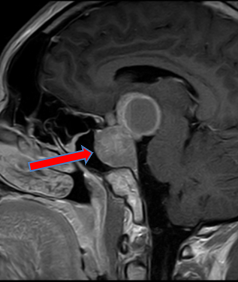

脳の奥深く、下垂体や脳室内で、内視鏡観察下に腫瘍を採取して病理診断をおこなったり、腫瘍を摘出することも可能です。

下垂体腫瘍の分野は神経内視鏡手術がもっとも進んでいます。脳の中央底面に位置する下垂体の腫瘍は、従来、鼻の穴、唇の下からのアプローチで手術用顕微鏡下で行うのが一般的でしたが、最近は鼻の穴から鼻腔を経由し下垂体部分まで内視鏡を到達させ腫瘍を取り除く手術が行われています。手術の際の鼻の粘膜の損傷も少なく安全に手術ができます。

下垂体腫瘍(矢印)のMRI画像